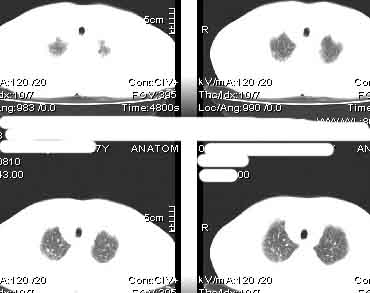

该病例我的诊断意见:右肺上叶周围型肺癌伴纵隔和右肺门淋巴结增大和右肺上叶阻塞性肺炎{病灶周围致密影以近肺门侧明显!}。右侧少量胸腔积液。

一. 1)症状有无发热及慢性过程.2)化验室检查?3)有无tb接触史?二.右肺上叶见片团状影,边界欠清,外侧方见一结节状软组织影,密度欠均匀,内可见低密度坏死区.周围强化明显,肺内见纤维索条影,局部胸膜增厚,但无明确胸膜凹陷.上叶支气管壁增厚,肺门及纵隔淋巴结增大.右侧胸腔少量积液.诊断意见:1右肺上叶慢性感染性疾病(肺tb?)伴肺门,纵隔淋巴结大.右胸少量积液.右肺上叶结节影多为tb球?2右肺上叶周围型肺ca伴肺门,纵隔淋巴结转移待排.右肺上叶炎变(肺门及纵隔淋巴结压迫).右胸少量积液.等待随返结果.